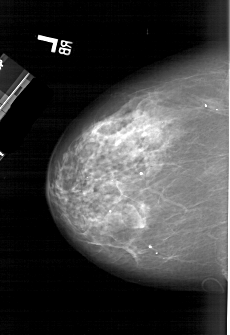

A_1987_1.RIGHT_MLO

RIGHT_CC LINES 6121 PIXELS_PER_LINE 4216 BITS_PER_PIXEL 12 RESOLUTION 43.5 OVERLAY

FILE: A_1987_1.RIGHT_CC.OVERLAY

TOTAL_ABNORMALITIES 1

ABNORMALITY 1

LESION_TYPE MASS SHAPE IRREGULAR MARGINS ILL_DEFINED

ASSESSMENT 4

SUBTLETY 4

PATHOLOGY MALIGNANT

TOTAL_OUTLINES 1

BOUNDARY